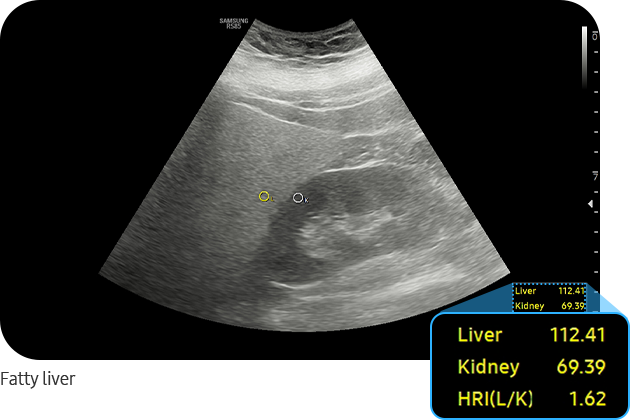

EzHRI™ places 2 ROIs on the liver parenchyma and renal cortex and provides HRI* ratio. It offers convenience and an improved workflow by suggesting initial ROIs, calculates the average brightness ratio of the liver parenchyma and the renal cortex.